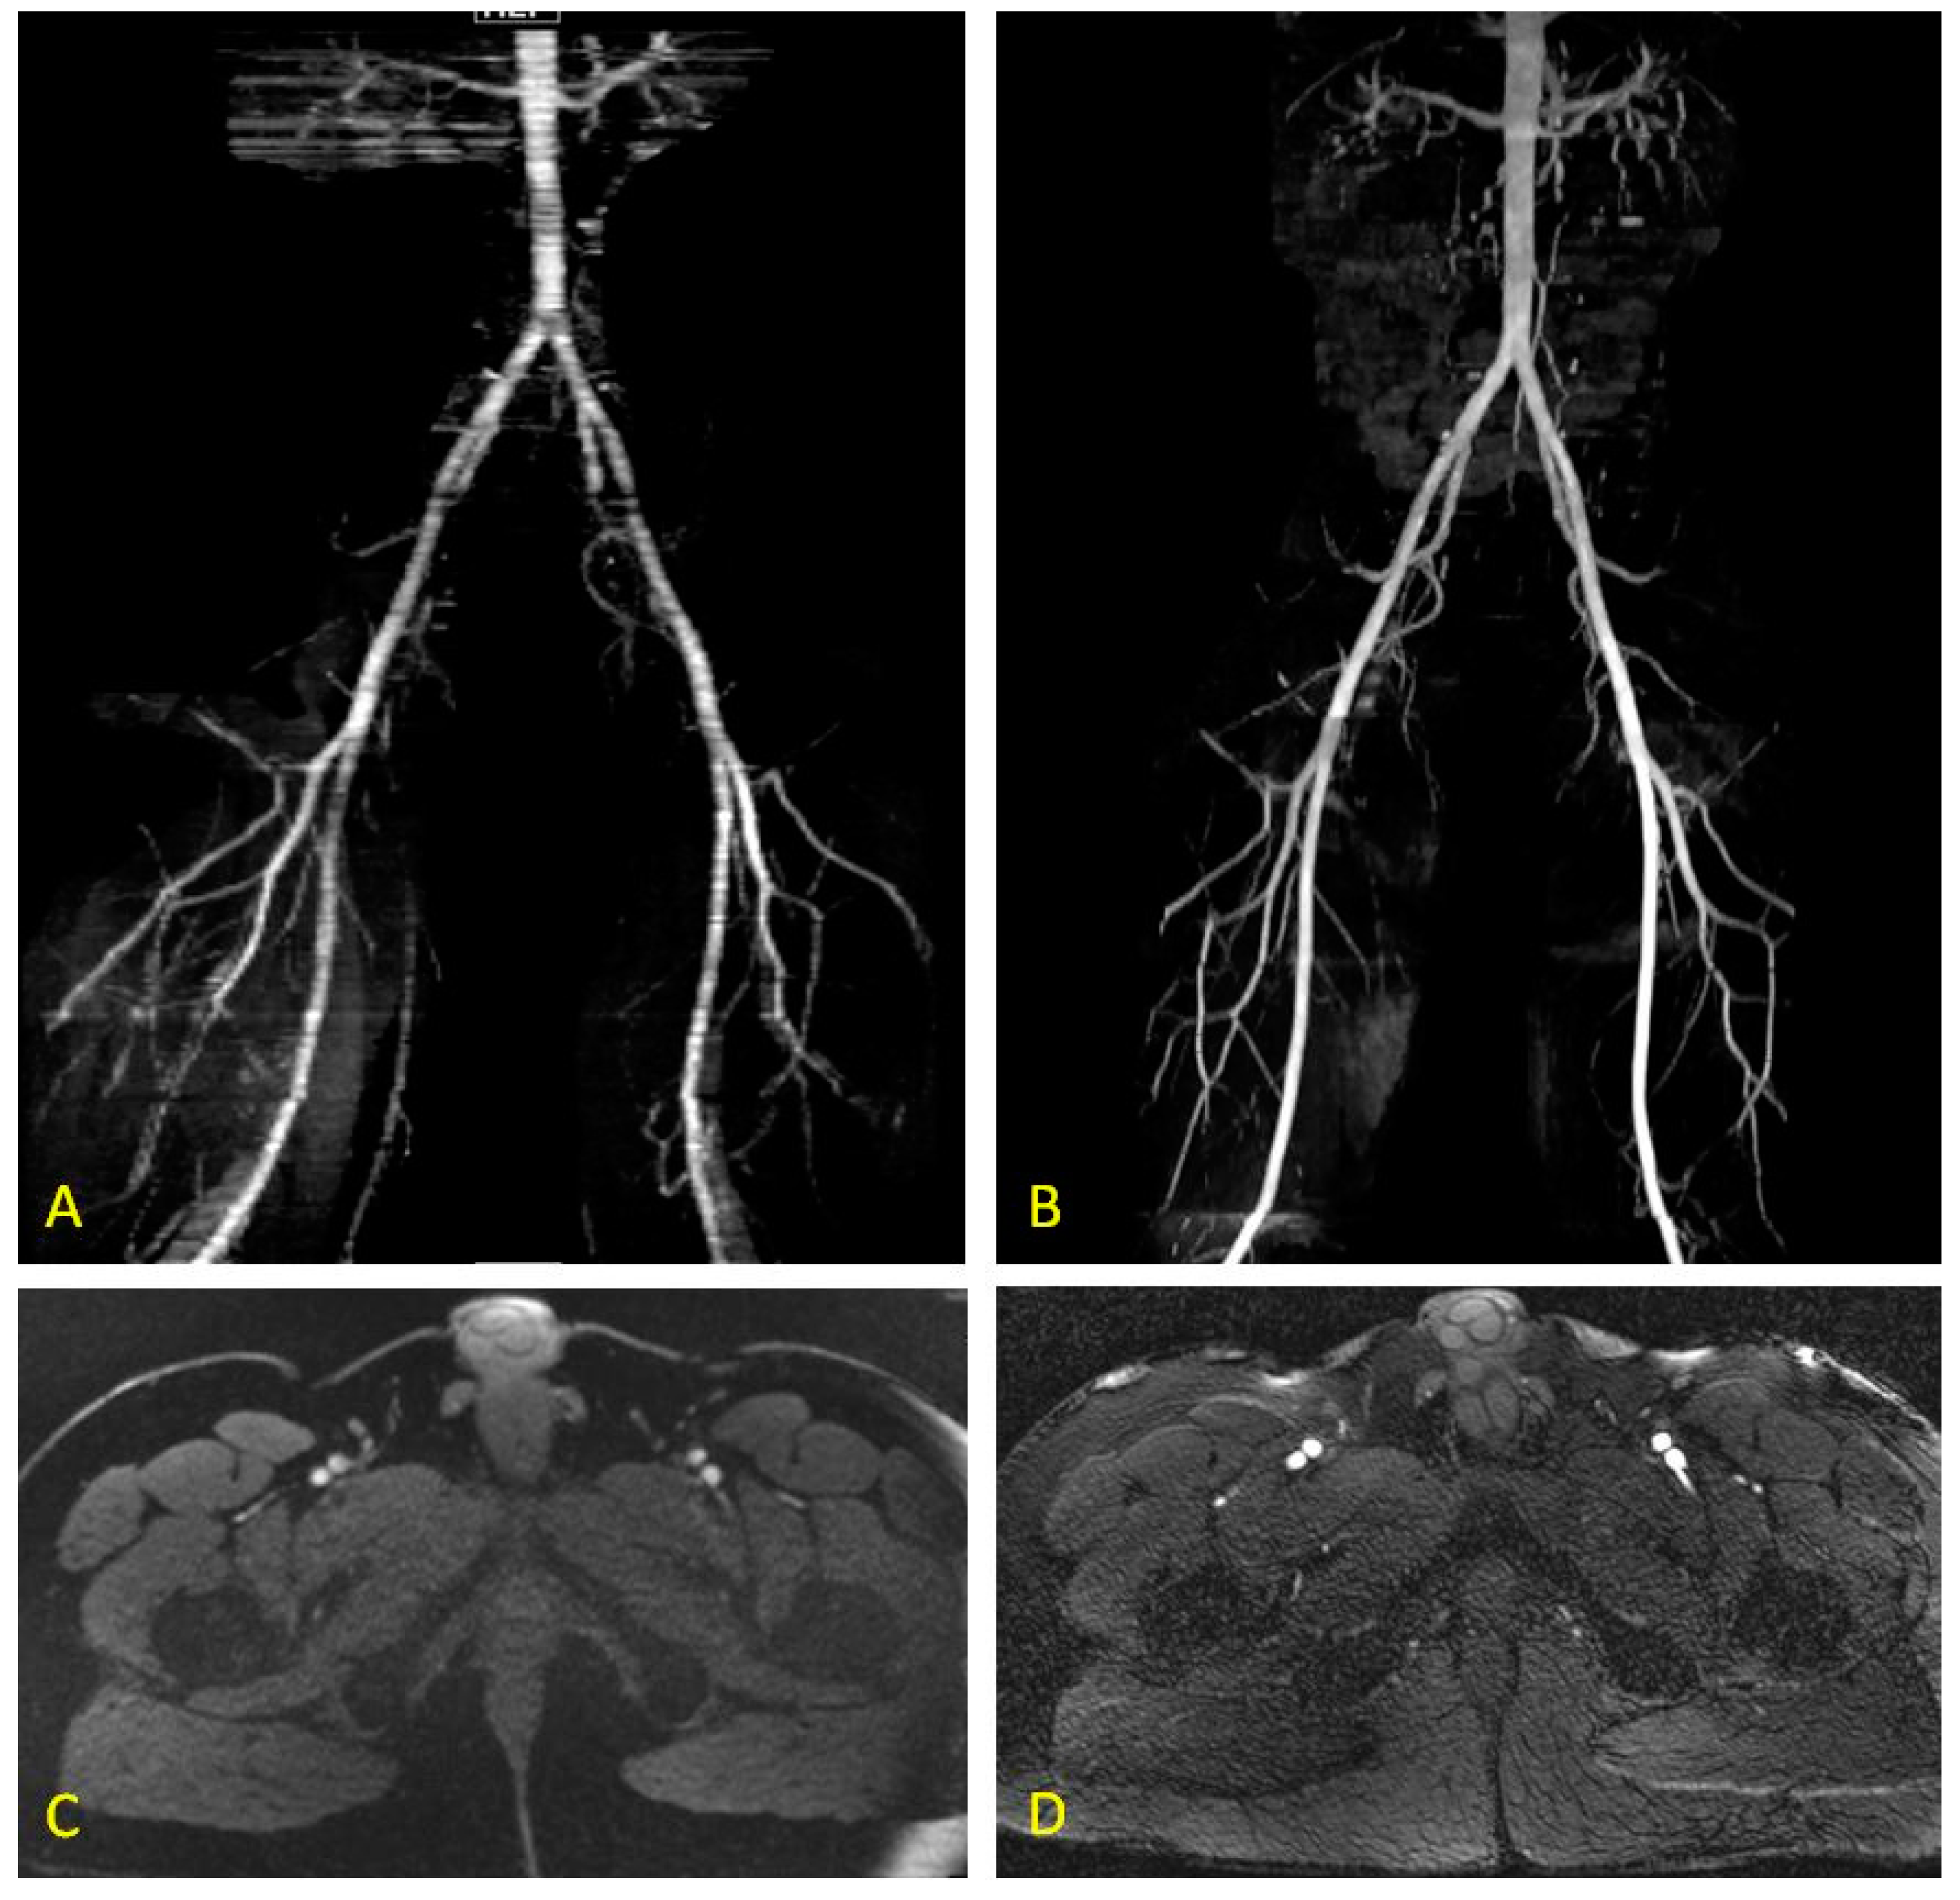

2.5. Quiescent-Interval Single-Shot MRA

3.1. QISS: Technical Considerations and Early Feasibility studies

3.2. Comparisons with Existing Non-Invasive Diagnostic Techniques

3.3. Comparison to Non-Enhanced MRA Techniques